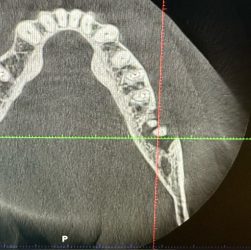

Case I got yesterday. Patient really wants an implant at #18 site. Fun case! ~60yo female, non-smoker, no DM, no osteoporosis or any other bone-related diseases.

How does one clean that PARL adequately, avoid disturbing the IA, and graft reliably. That is a fun case!